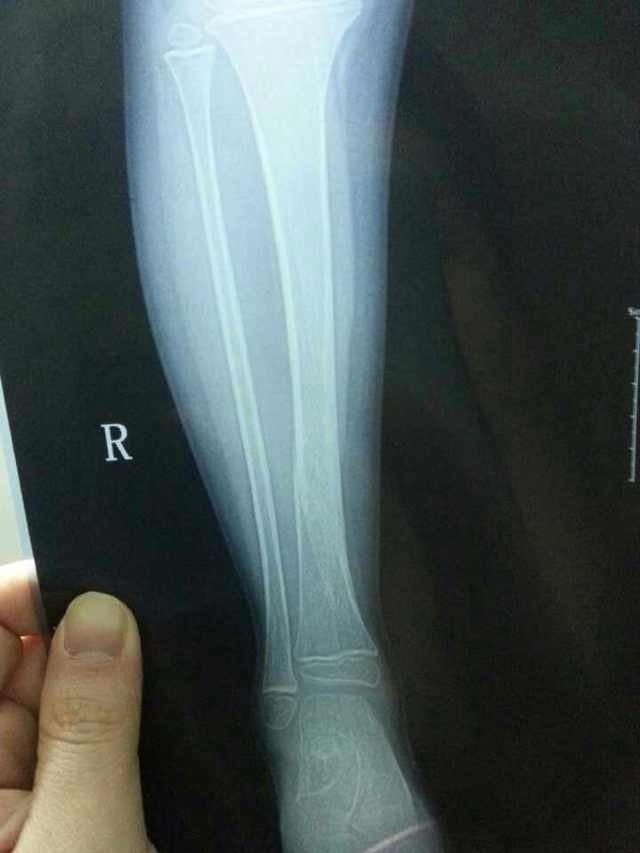

4岁小孩子胫骨骨折9周了可以走路吗:她现在都在走路了:不知道有没有影响 点击展开 匿名用户 2014-02-26 01:19 为您推荐: 其他回答 病情分析: 你好,从片子看骨痂生长很好。 指导意见: 9周2个月,可以适当下地活动,但是一定要注意不能奔跑,最好是在大人监督下活动。 匿名用户 2014-02-26 10:07 相关问题 八岁孩子胫骨骨折三个多月了,走路有点瘸怎么办 现在怀孕30周了,现在走路肚皮都觉得疼,也不知道什么原因? 现在我怀孕38周,不知道是不是孩子入盆了,走路的时候有些痛